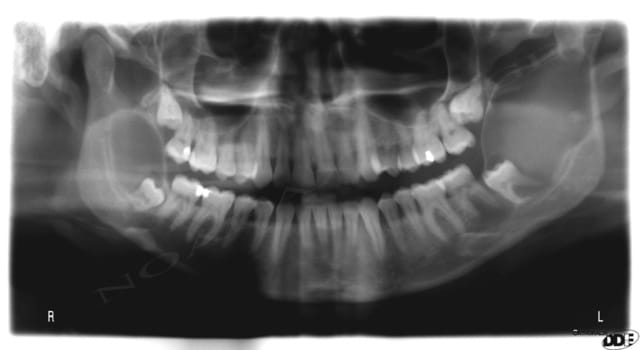

j'ai le scan mais pas ici la corticale linguale est reduite à sa plus simple expression et le kyste remonte sur le trajet du nerf et s'etend aussi en vestibulaire

A priori vu l'évolution sur les radios et l'âge de la patiente je pense qu'il s'agit d'un kératokyste en première intention.

éventullement un améloblastome.

ça peut être également un kyste dentigère laissé en place car il me semble que le kyste est déjà présent sur la première pano et elle est en rapport partiel avec le collet de 38 enclavée mais ça n'est pas caractéristique.

DOnc pour résumé:

1. kératokyste

2. kyste dentigère "oublié"

3. améloblastome unikystique